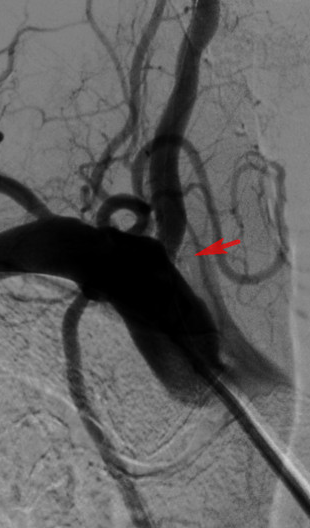

杨老伯的这次手术,也是我院首次使用药物涂层支架治疗椎动脉狭窄。术中,在贾军主任的指导下,董广宇副主任医师介入团队顺利实施椎动脉开口球囊成形及药物涂层支架置入手术,术后椎动脉开口基本恢复至正常大小。

手术非常成功。